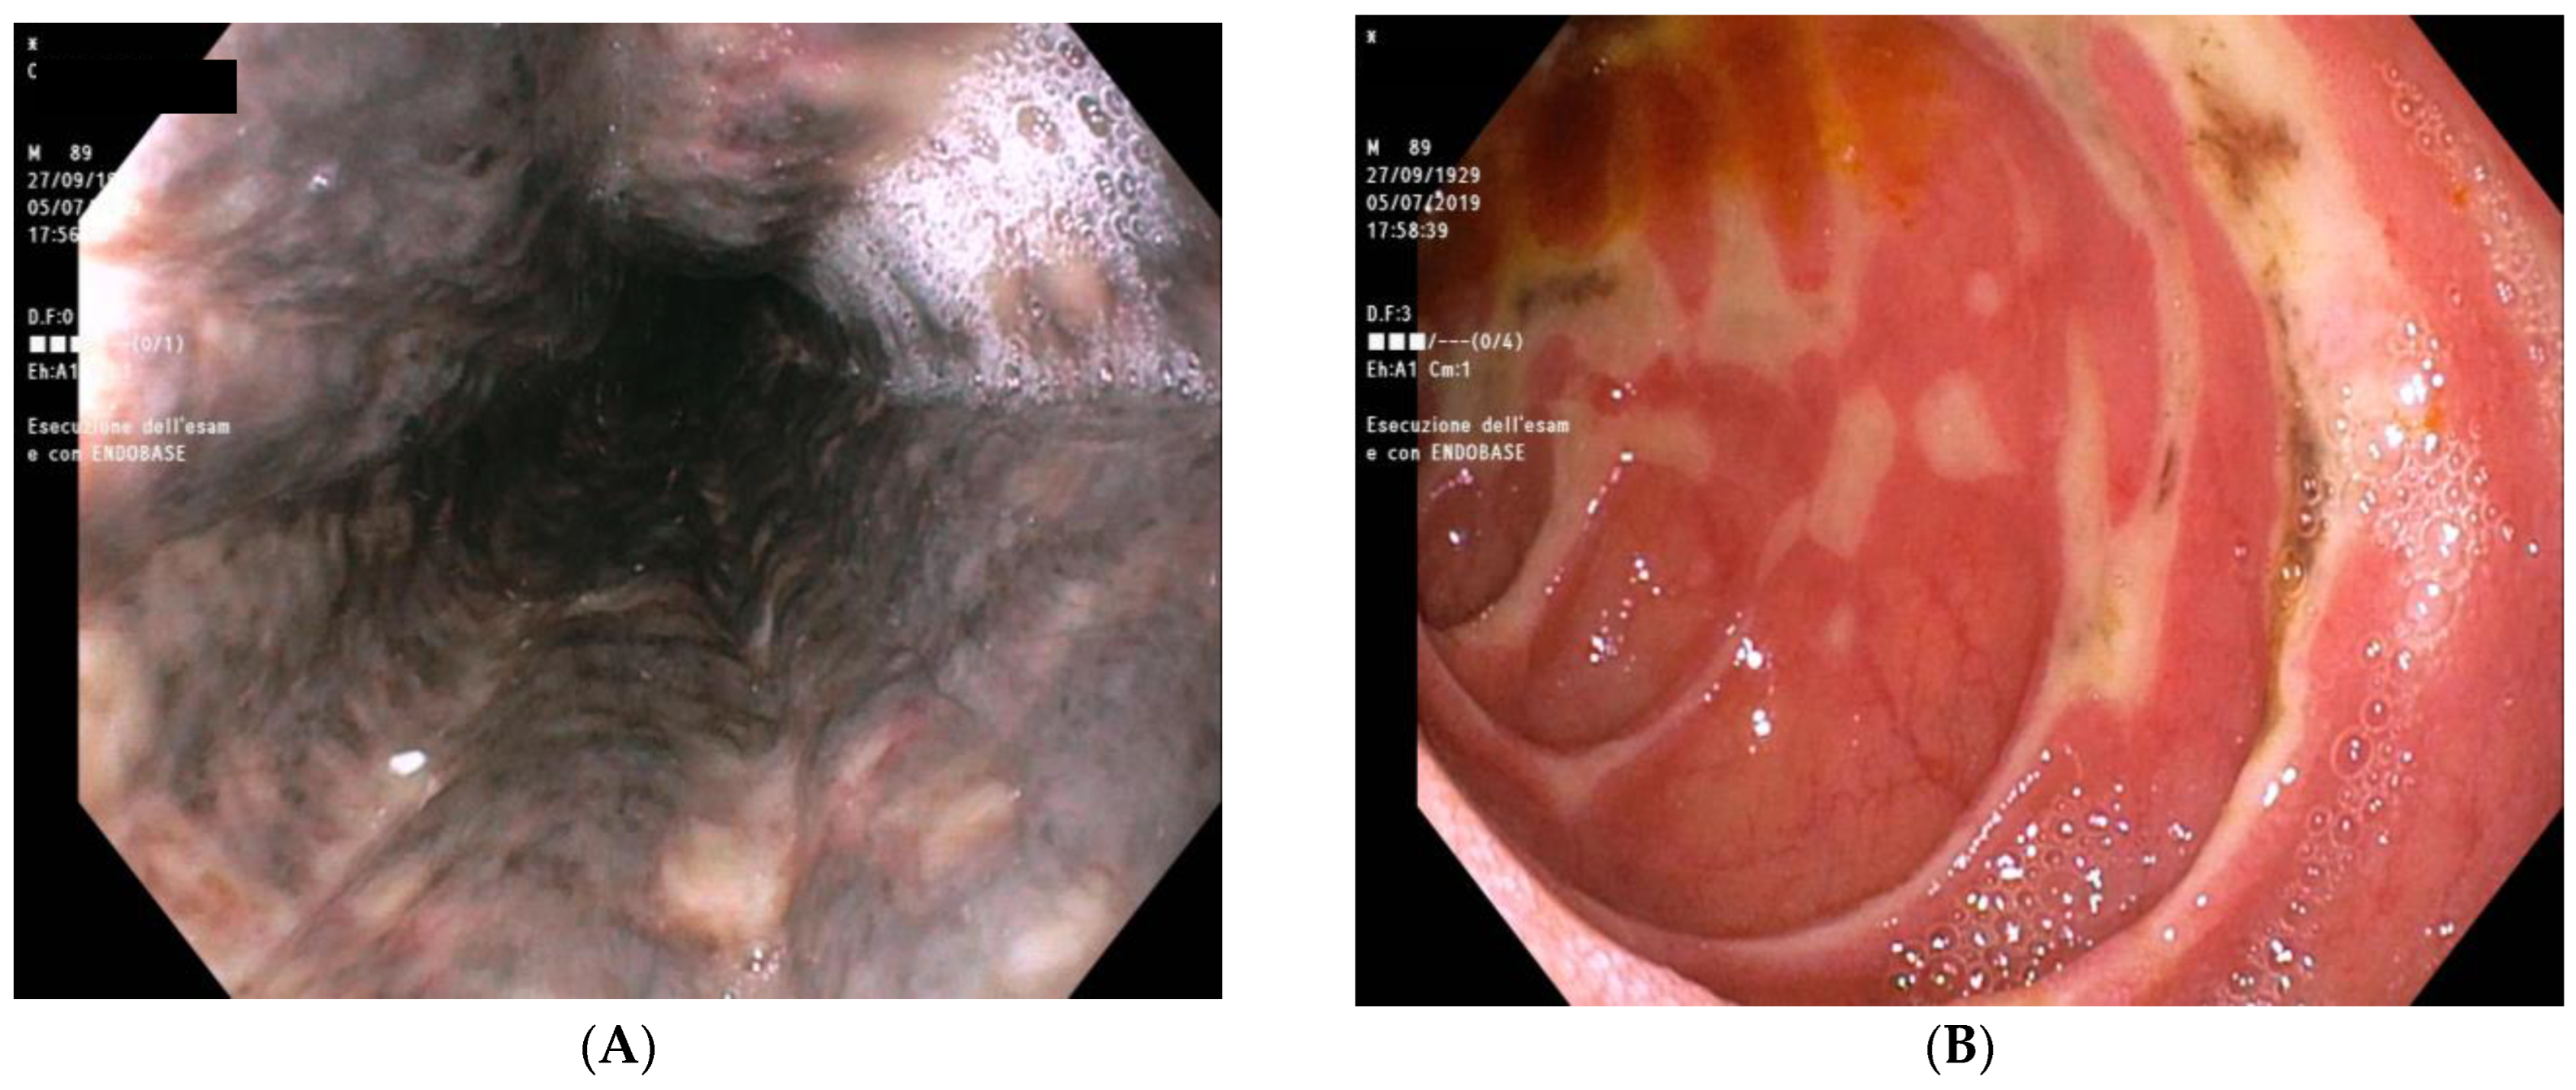

Further evaluation included an esophagogastroduodenoscopy (EGD) that demonstrated black circumferential necrosis of the mid and distal esophagus, which abruptly terminated at the gastroesophageal junction (Figure 2A). Multiple irregular ulcers with black necrotic areas were also present in the bulb and second duodenal portion (Figure 2B). Esophageal biopsies showed necrotic debris without fungal hyphae or other pathogens.

Figure 2.

Esophagogastroduodenoscopy performed at first admission to the emergency department. (A) Black circumferential necrosis of the mid and distal esophagus; (B) ulcers with black necrotic areas in the bulb and second duodenal portion.